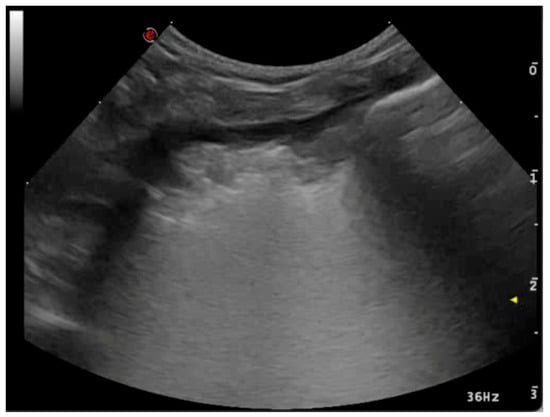

3.1.2. Pleural Effusion